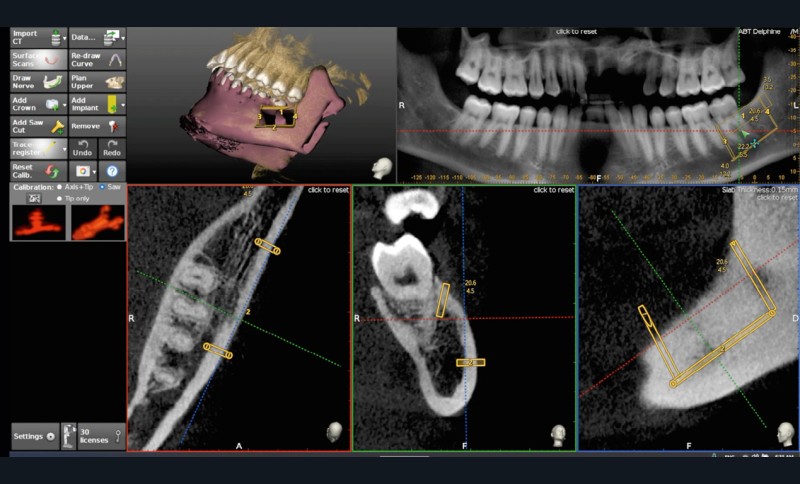

L’avènement des technologies numériques a permis d’améliorer la précision de ces procédures. La planification implantaire 3D, associée à la conception et fabrication assistée par ordinateur (CAD/CAM), permet aujourd’hui de concevoir des guides chirurgicaux spécifiques optimisant et sécurisant le positionnement des blocs osseux. De même, la démocratisation récente des techniques de chirurgie guidée dynamiques par caméra stéréoscopique constitue un outil attractif pour les techniques de reconstruction osseuse. Ainsi, la taille du bloc à prélever sur la zone rétromolaire mandibulaire peut aussi être exactement déterminée en amont de la chirurgie (fig. 1 et 2).

La possibilité de réaliser le prélèvement osseux en bloc avec un guide statique permet d’affiner sensiblement la quantité d’os prélevée en fonction du besoin réel et diminuer la morbidité du geste. En revanche, le positionnement même du guide nécessite l’ouverture d’un lambeau de grande taille.